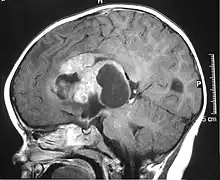

| MRI of an AT/RT | |

The initial diagnosis of a tumor is made with a radiographic study (MRI[22] or CT-). If CT was performed first, an MRI is usually performed as the images are often more detailed and may reveal previously undetected metastatic tumors in other locations of the brain. In addition, an MRI of the spine is usually performed. The AT/RT tumor often spreads to the spine. AT/RT is difficult to diagnose only from radiographic study; usually, a pathologist must perform a cytological or genetic analysis.

Appearance on radiologic exam

AT/RTs can occur at any sites within the CNS; however, about 60% are located in the posterior fossa or cerebellar area. The ASCO study showed 52% posterior fossa; 39% sPNET; 5% pineal; 2% spinal, and 2% multifocal.[3]

The tumors' appearance on CT and MRI are not specific, tending towards large size, calcifications, necrosis (tissue death), and hemorrhage (bleeding). Radiological studies alone cannot identify AT/RT; a pathologist almost always has to evaluate a brain tissue sample.

The increased cellularity of the tumor may make the appearance on an uncontrasted CT to have increased attenuation. Solid parts of the tumor often enhance with contrast MRI finding on T1 and T2 weighted images are variable. Precontrast T2 weighted images may show an isosignal or slightly hypersignal. Solid components of the tumor may enhance with contrast, but not always. MRI studies appear to be more able to pick up metastatic foci in other intracranial locations, as well as intraspinal locations.

Preoperative and follow-up studies are needed to detect metastatic disease.